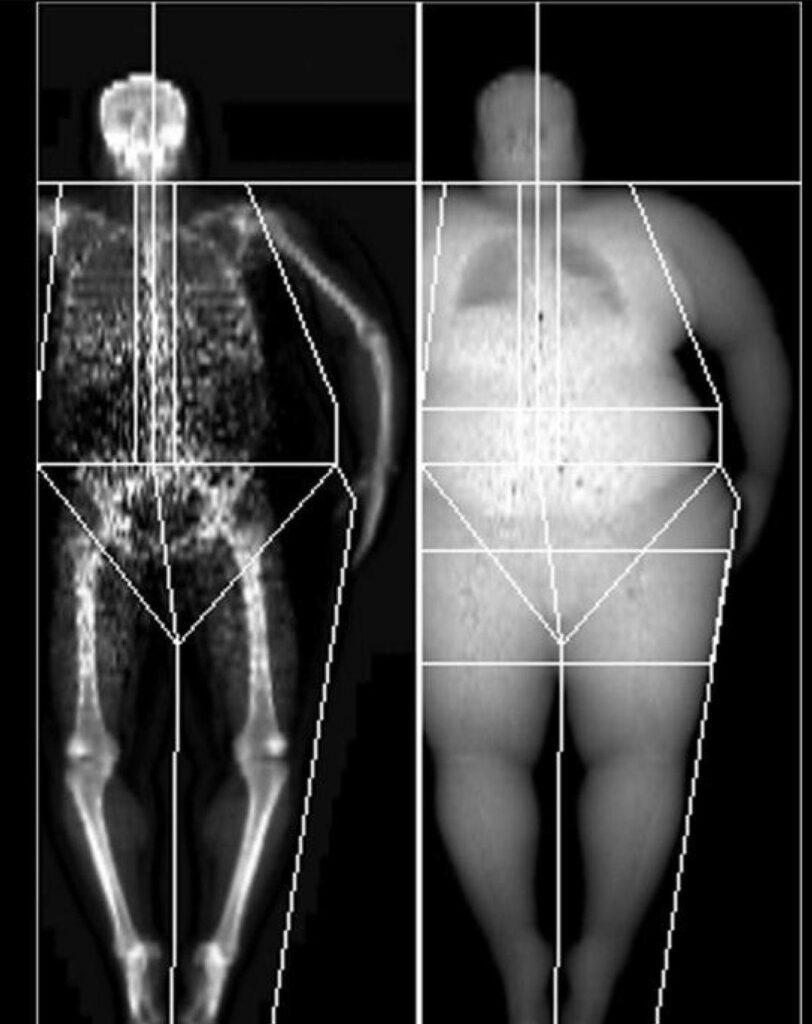

El factor predictivo más preciso de fractura de cadera es la densidad mineral ósea (DMO) de la cadera, medida mediante la técnica de absorciometría de rayos X de energía dual (DXA). La DMO es una medida que cuantifica la cantidad de minerales, especialmente calcio, presente en el tejido óseo. Una DMO baja indica una fragilidad ósea, lo que conlleva un mayor riesgo de fracturas. En este contexto, la cadera es un lugar crítico para evaluar la DMO debido a la gravedad de las fracturas de cadera y sus graves consecuencias para la salud y la calidad de vida. Las fracturas de cadera pueden resultar en una pérdida significativa de movilidad, discapacidad a largo plazo, hospitalización prolongada y tasas de mortalidad más altas, especialmente en personas de edad avanzada.

La relación entre la DMO y el riesgo de fractura es inversa, lo que significa que una DMO más baja se asocia con un mayor riesgo de fractura de cadera. Este vínculo ha sido demostrado repetidamente en estudios epidemiológicos, respaldando la DMO medida con DXA como un factor predictivo sólido.

✳️ La medición de la densidad mineral ósea en la cadera mediante la DXA es un predictor altamente preciso de fracturas de cadera. La relación inversa entre DMO baja y riesgo de fractura es respaldada por una sólida base de evidencia científica, y esta información es fundamental para la evaluación de riesgo individual, la toma de decisiones terapéuticas y el seguimiento de la efectividad del tratamiento. Detectar y abordar tempranamente la pérdida de densidad ósea es esencial para prevenir fracturas y mejorar la calidad de vida, especialmente en poblaciones vulnerables, como las personas mayores.